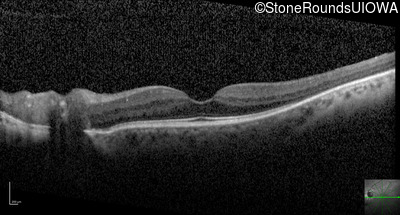

Optical Coherence Tomography - Left - 20/25

Exemplar / OCT Stack